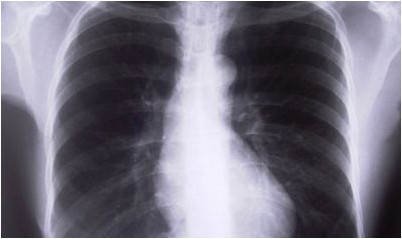

Дабы проверить на TB, медицинский работник будет применять стетоскоп, дабы слушать легкие и проверит на набухание в лимфатических узлах. Они кроме этого спросят о истории и симптомах заболевания, и оценке риска человека выделения к TB.

Самый распространенный диагностический анализ на TB есть кожной пробой, где маленькая инъекция туберкулина PPD, экстракт бактерии TB, сделана чуть ниже внутреннего предплечья. …